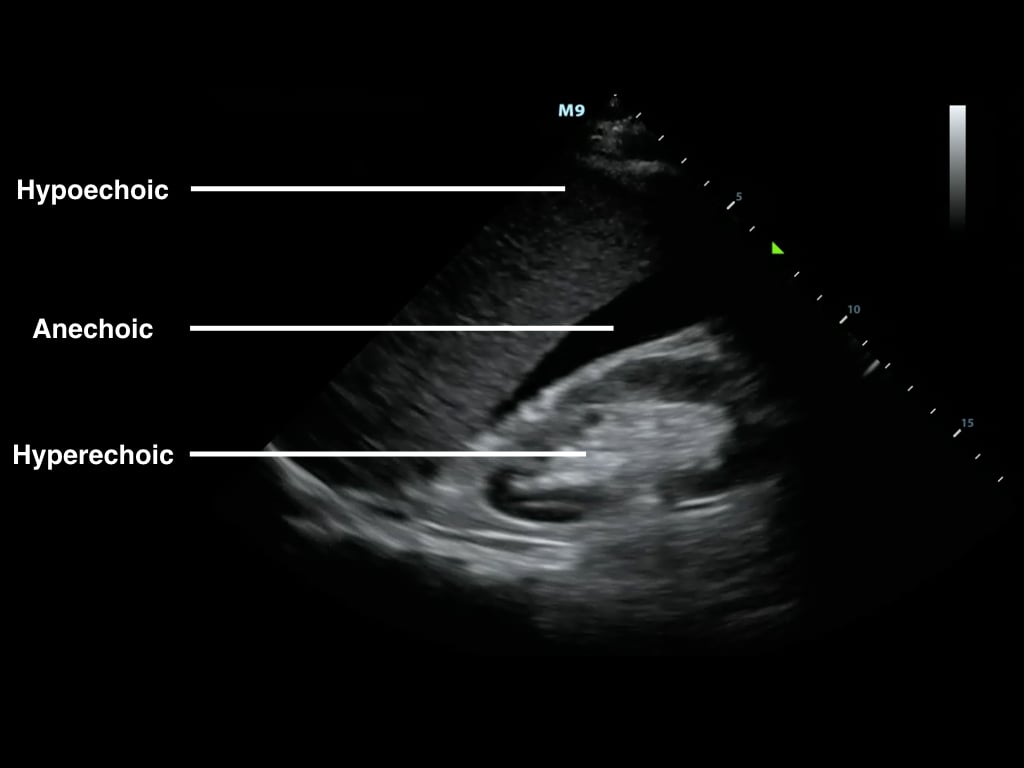

- B-mode or ‘brightness mode’ provides structural information utilizing different shades of gray (or different ‘brightness’) in a two-dimensional image (Figure 1)

- Figure 1. B-Mode image of free fluid in the right upper quadrant

- Brightness is determined by the amplitude of returning echoes

- Anechoic/Echolucent – Complete or near absence of returning sound waves, area is black

- Hypoechoic - Structure has very few echoes and appears darker than surrounding tissue

- Hyperechoic/Echogenic – Large amplitude of returning echoes appears brighter than surrounding tissue